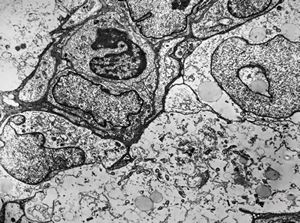

F,49y. | hemangioblastoma - brain